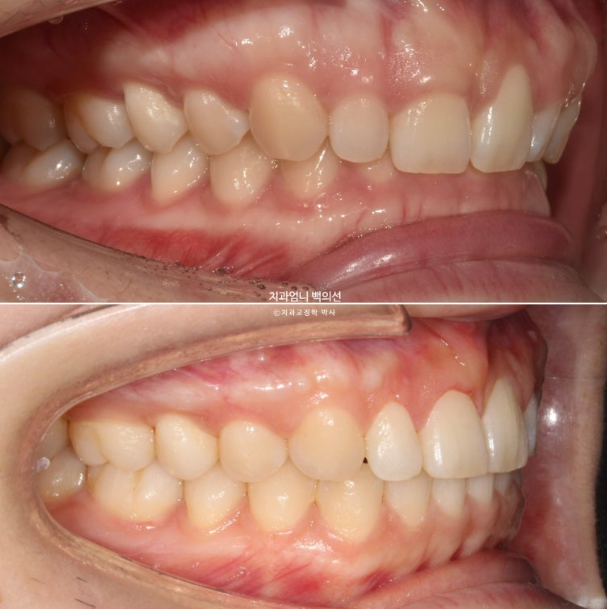

앞니가 뒤로 쓰러진 옥니이고

앞니가 옥니로 뒤로 쓰러져 있으면 앞니 뿌리 잇몸이 상대적으로 튀어나와 보이게 되며 잇몸돌출처럼 보이게 됩니다.

위 앞니 뿌리쪽 잇몸이 튀어나온 부분이 매끈해졌습니다

23.04~25.02

옥니 개선과 함께 뿌리가 뒤로 들어가면, 뿌리를 덮는 잇몸도 뒤로 들어갑니다.

측모에서는 뒤로 쓰러진 옥니 각도 개선이 잘 보입니다.

활짝 웃으면 옥니 개선도 잘 보입니다.